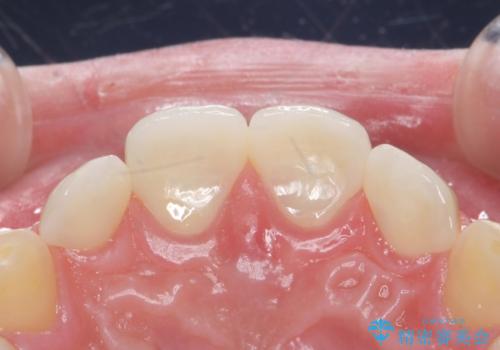

- 前歯の隙間を埋めたいとのことで来院された患者様です。

矯正治療とかぶせ物での治療どちらともご提案したところ、かぶせ物での治療をご希望されたためクラウンでの審美性回復を試みることとなりました。

形のイメージを反映させた仮歯を調整し、技工士さんと連携して製作したため口元に調和した非常に審美的なクラウンを装着することができました。